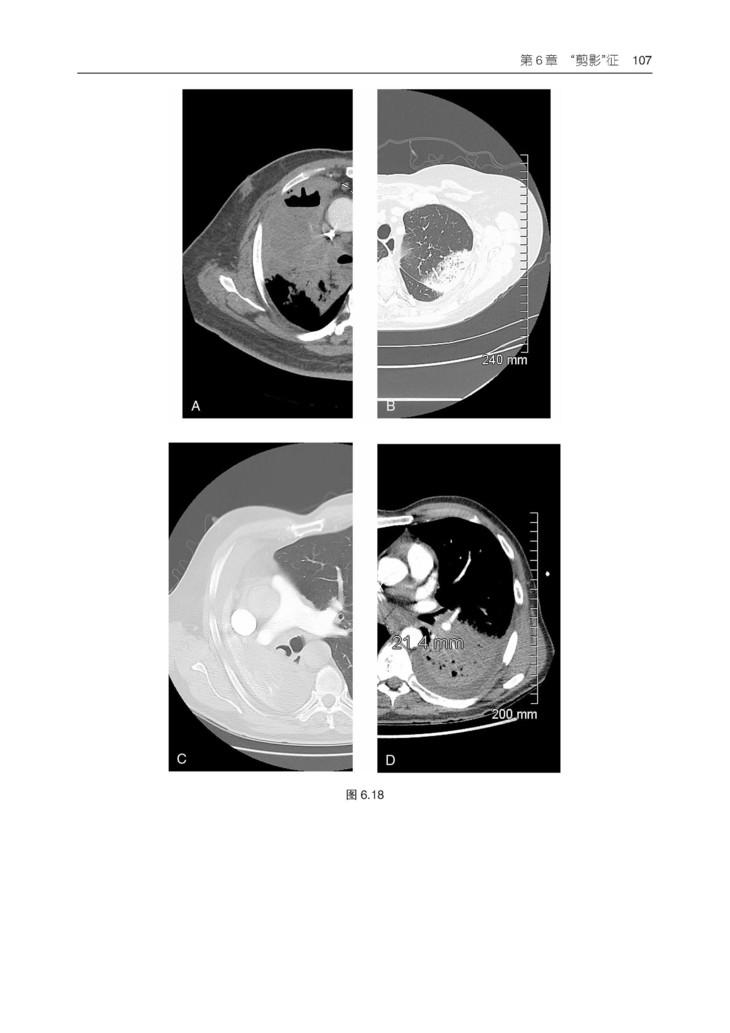

本书易于阅读、引人入胜,长期以来一直是广大放射科医学生和医生的首选学习资源。本书提供了有关胸部影像学方面的所有内容,包括病理学和解剖学难题,以通俗易懂的方式对基础理论、影像判读方法和专业术语进行了阐释。紧跟学科前沿,包括胸膜肺实质纤维弹性组织增生症、合并肺纤维化与肺气肿、与年龄相关的肺部变化、间质性肺病、肺癌筛查和肿瘤分类,以及降低辐射剂量和安全考虑等热点话题。

3.包含550 余幅高质量影像图片,并根据需要配有相关的PET、CT 和 MRI 图像。